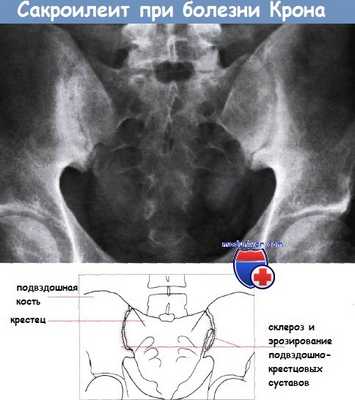

а - ирит при болезни Крона. Выраженная конъюнктивальная инфекция, гипопион.

б - терминальный илеит при болезни Крона. Илеоскопия при колоноскопии.

в - рецидив болезни Крона после резекции: поражена оставшаяся часть терминального отрезка подвздошной кишки.

г - язвы в тощей кишке при болезни Крона. Капсульная эндоскопия.